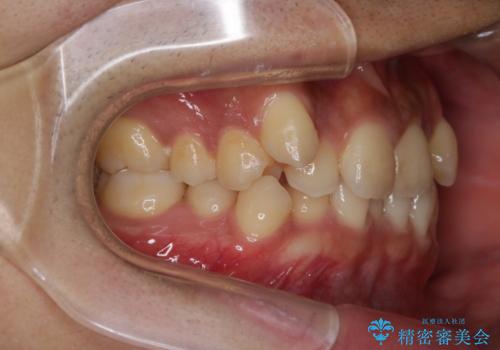

インビザライン単独でここまでできる!!抜歯矯正

1日20時間以上、正しくインビザラインを使用して頂いたおかげで、ワイヤーに切り替えることなく矯正治療を終了することが出来ました。周囲からも歯並びがすごく綺麗になったと言われたのことで大変ご満足いただけました。